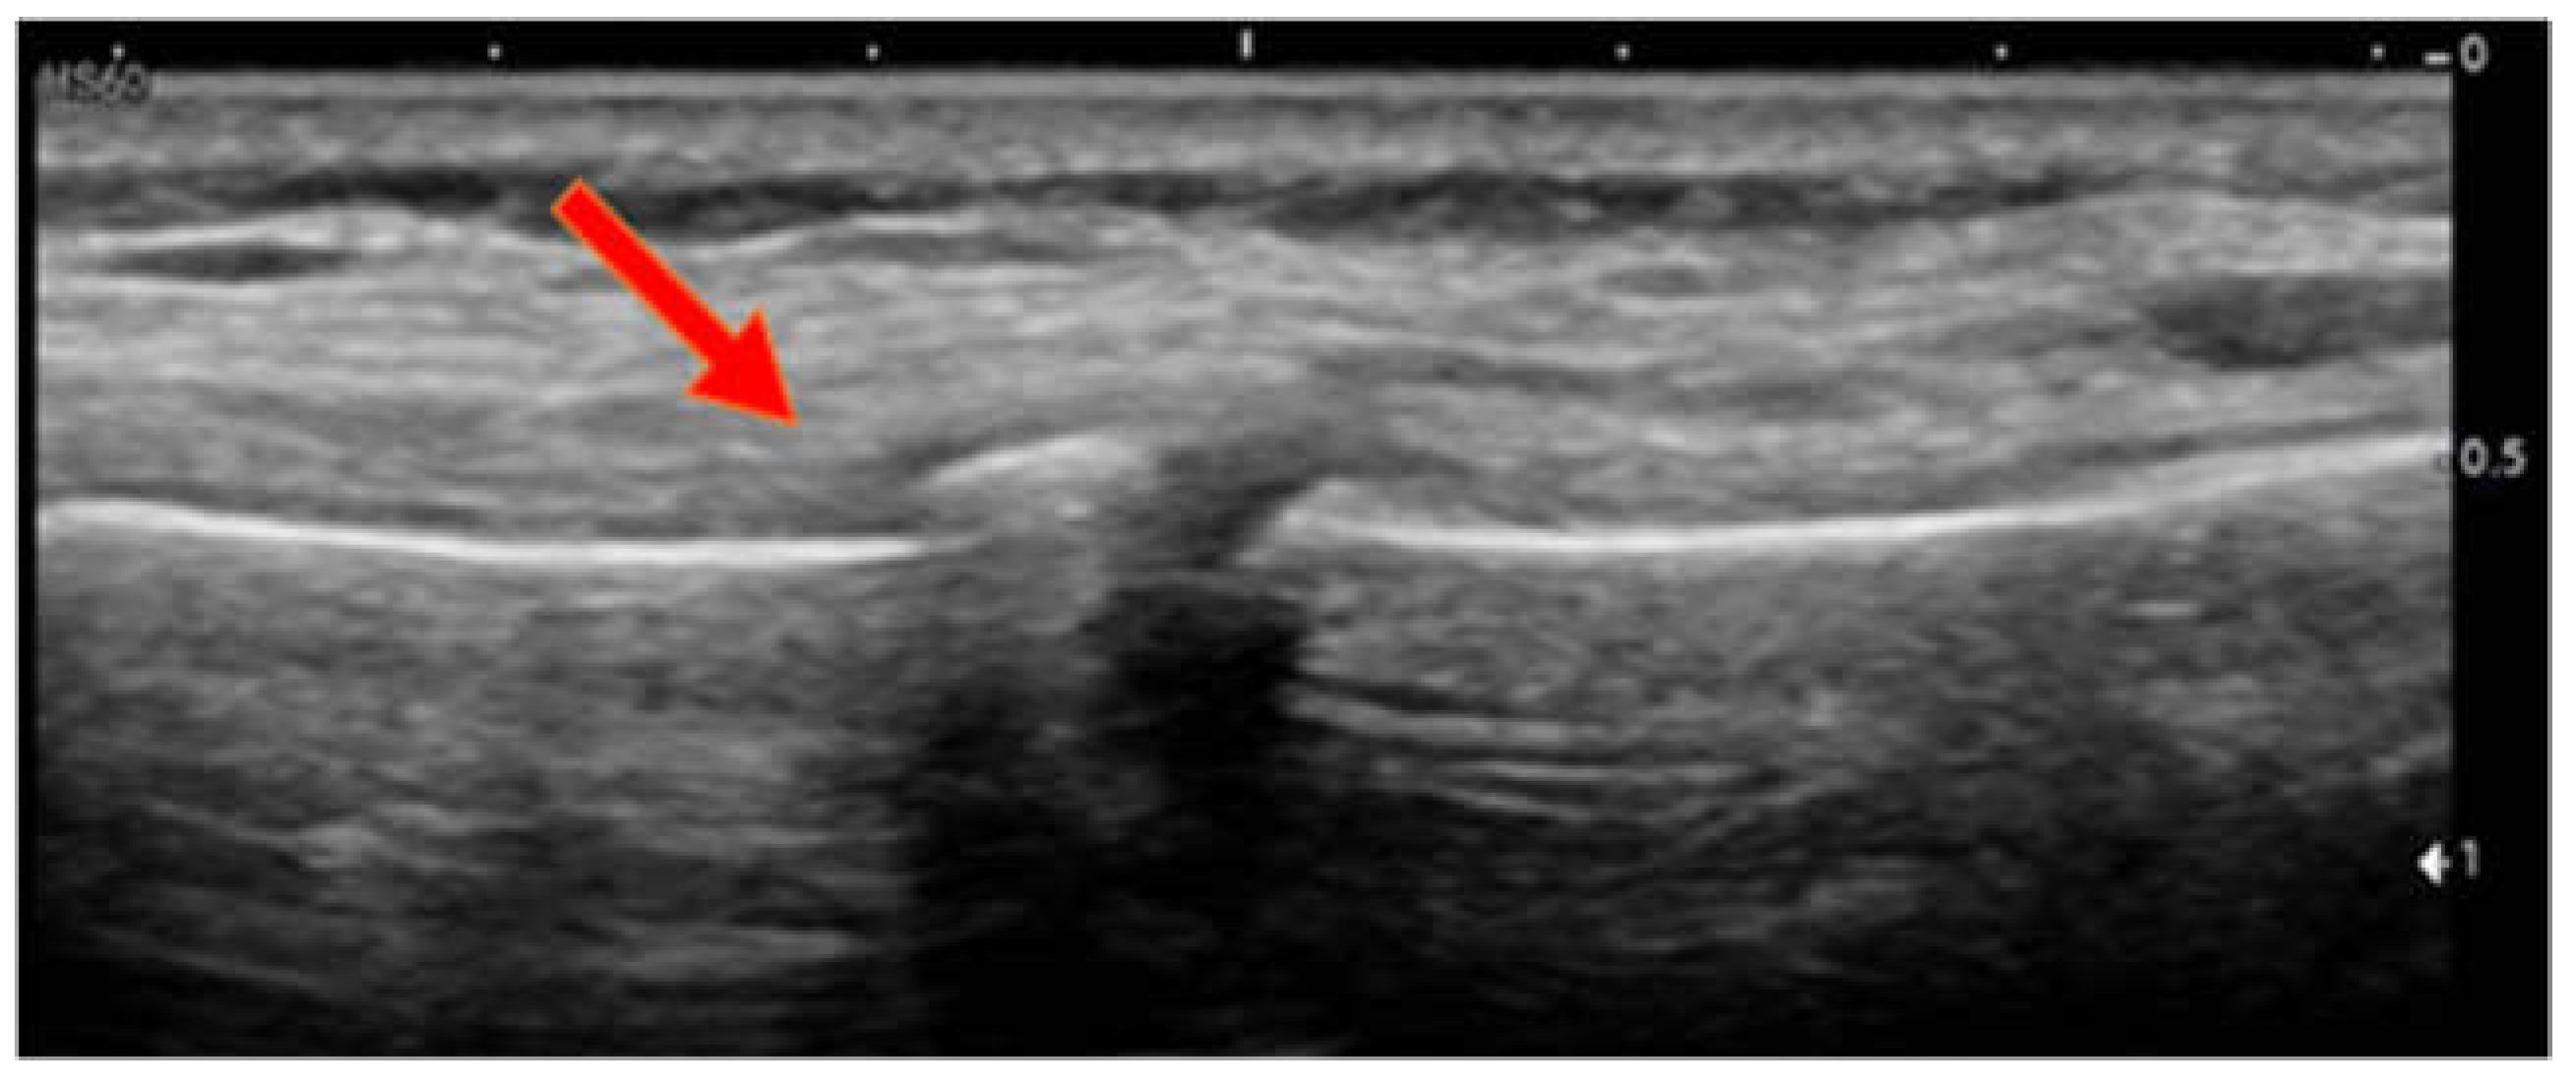

POCUS Diagnosis of Sternal Fractures in Children without Direct Trauma—A Case Series

- Sesia, S.B.; Prüfer, F.; Mayr, J. Sternal Fracture in Children: Diagnosis by Ultrasonography. Eur. J. Pediatr. Surg. Rep. 2017, 5, e39–e42. [Google Scholar] [CrossRef]